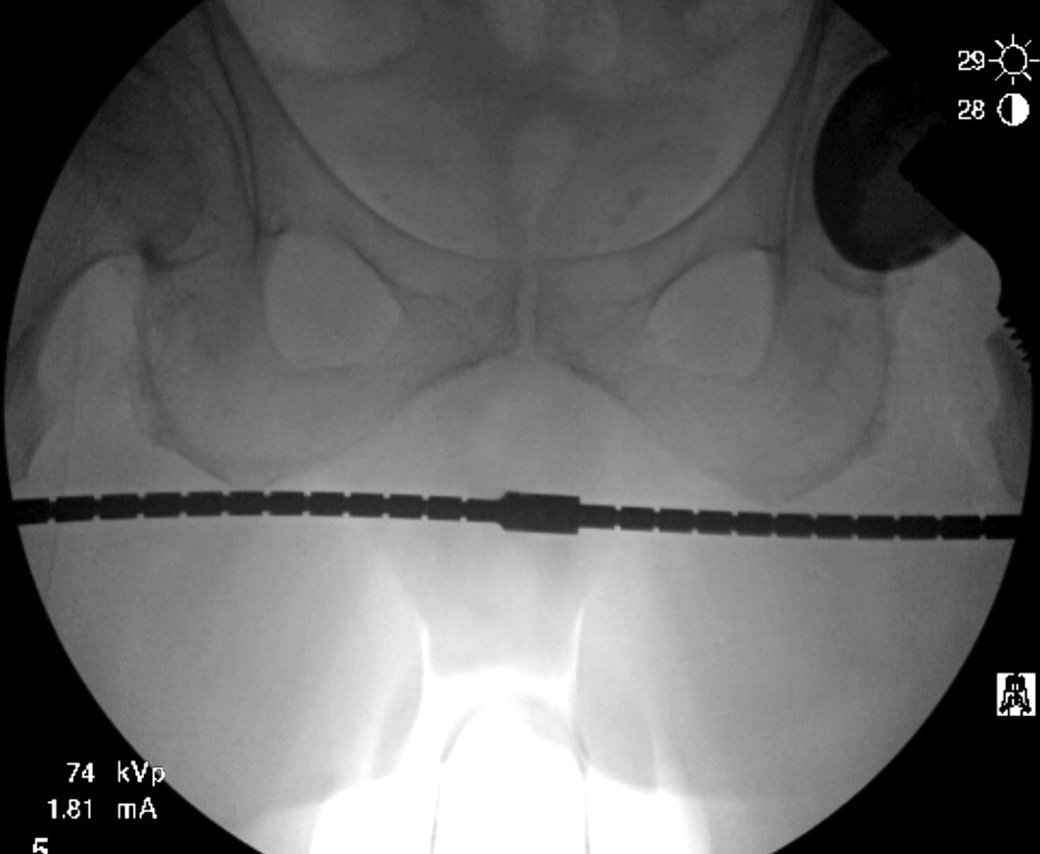

For use during intraoperative imaging while performing anterior hip arthroplasty to help determine implant fit, position, alignment and recreation of leg length and offset using the contralateral hip for reference

Designed to be overlayed on the pelvis during the imaging part of the procedure to compare leg length and offset to the contra lateral hip using the trans teardrop or trans ischial line as reference.

Notched in increments of 1 cm for ease of reference.